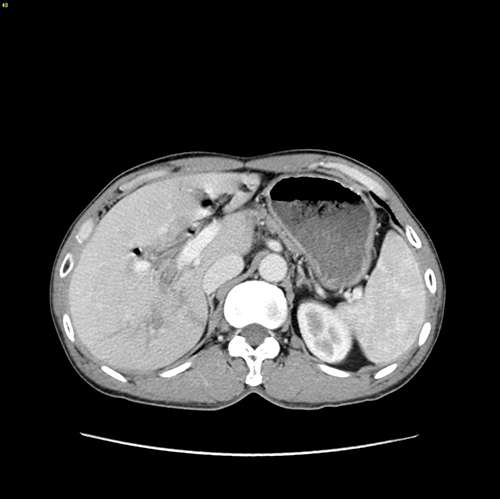

右肝内胆管结石、 胆管十二指肠瘘--S67肝切除、胆肠吻合、十二指肠瘘修补